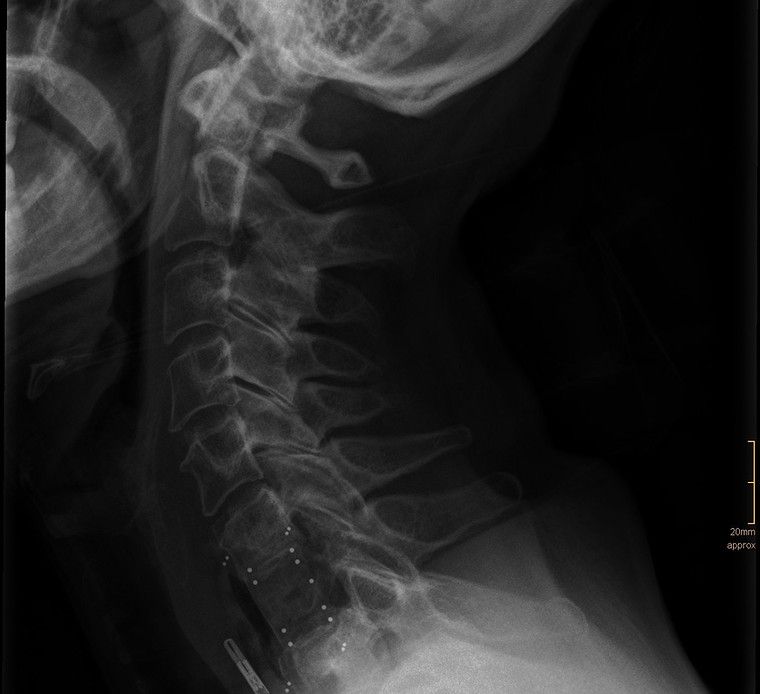

Als Facharzt für Orthopädie lag mein Schwerpunkt als Oberarzt im Wirbelsäulenteam des AKH Wien von 2019 bis 2024 auf der operativen Versorgung von Erkrankungen der Wirbelsäule. In den vergangenen Jahren habe ich viele hundert Wirbelsäulenoperationen durchgeführt – von mikrochirurgischen Eingriffen bis hin zu minimalinvasiven rekonstruktiven Verfahren. Dank meiner langjährigen Erfahrung verfüge ich über besondere Expertise in Bandscheibenoperationen, Dekompressionen sowie in der chirurgischen Behandlung schwerer Wirbelsäulenpathologien. Diese Eingriffe erfordern höchste Präzision, Sorgfalt und ein tiefes Verständnis der individuellen Krankheitsbilder. Besonders wichtig ist mir dabei, Sie umfassend zu beraten und gemeinsam mit Ihnen die für Sie beste Therapieentscheidung zu treffen. Ich nehme mir ausreichend Zeit für Ihre Fragen und sorge dafür, dass Sie sich medizinisch wie menschlich gut aufgehoben fühlen.

Es werden mikrochirurgische Bandscheibenoperationen und Dekompressionen durchgeführt.